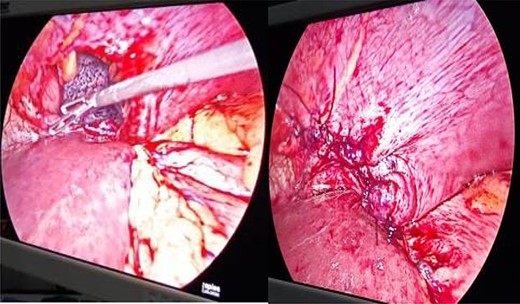

Patients were placed in right lateral position with head end slightly elevated (20–30°). The defects were identified, contents (if any) were reduced and the defects were closed with polypropylene suture (Fig. 4).

Defect in left hemidiaphragm with visible collapsed lung and closure of defect.

Closed defects were strengthened with mesh (Fig. 5).